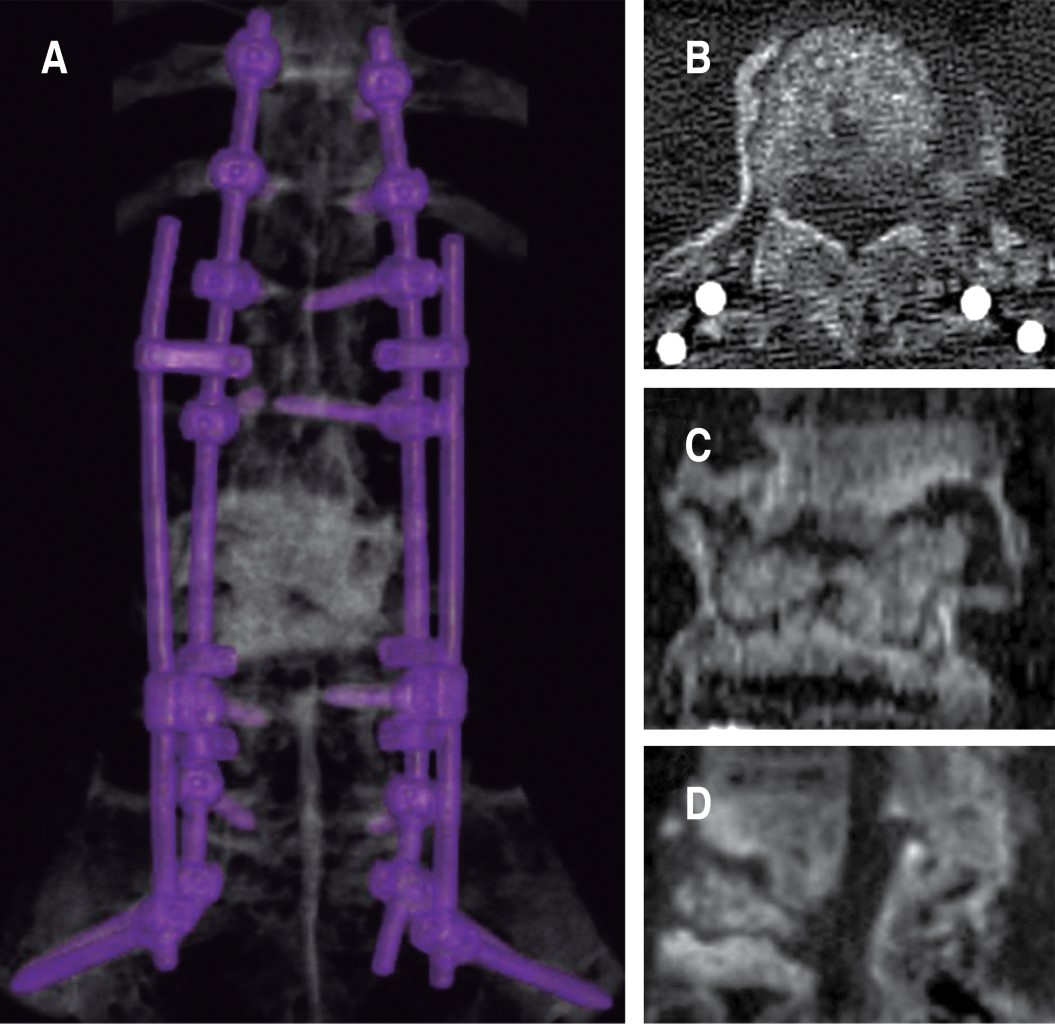

Se realizó artrodesis toracopélvica de T10 a iliacos, por abordaje posterior con doble barra de titanio y conectores, con una guía 3D y agujas de Kirschner, se realizó colocación de tornillos sacroilíacos; se resecó callo óseo y, con ayuda de un embudo a través del pedículo derecho de L3, se colocó injerto óseo autólogo en el espacio del cuerpo de L3 con fluoroscopio. Sangrado de 1,200 ml, se transfundió un paquete globular. El paciente egresó a los tres días (Figuras 5, 6 y 7).

A las dos semanas, en la tomografía se observó la artrodesis y el cambió de densidad ósea tras la colocación de injerto autólogo en cuerpo de L3 (Figura 8). En su cita de seguimiento a los 15 días el paciente presentaba disminución de dolor mecánico.